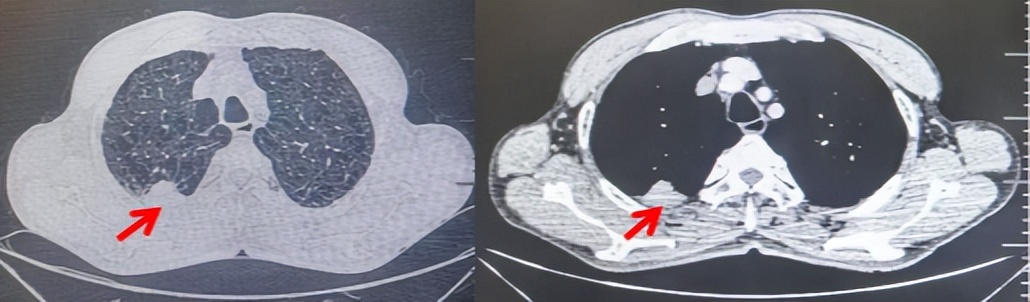

2024.11.19患者出现右侧胸痛,复查胸部CT检查示右侧胸膜肿物,大小约31mmX24mm,右侧4、5肋骨骨质破坏,考虑转移(如图2)。建议患者穿刺活检取病理明确诊断,患者拒绝,经MDT会诊后结合影像学表现及病史考虑为胸膜转移,肋骨转移,分期为rT0N0M1a IVA期,DFS仅仅17个月。2024.12.05起行信迪利单抗联合培美曲塞+卡铂方案治疗4周期,复查胸CT评效PR(如图3)。之后给予信迪利单抗+培美曲塞维持治疗6周期,期间复查CT评效PR(如图3)。目前信迪利单抗+培美曲塞维持治疗中,截止至目前PFS约为8个月,治疗期间未出现明显毒副反应。

图2:患者胸膜及肋骨转移(2024.11)胸部CT肺窗、纵隔窗及骨窗

图3:患者免疫联合化疗治疗后胸部CT,(A、B)图展示信迪利单抗联合培美曲塞+卡铂治疗

4周期(2025.02)疗效,(C、D)图展示信迪利单抗+培美曲塞维持治疗6周期(2025.07)疗效